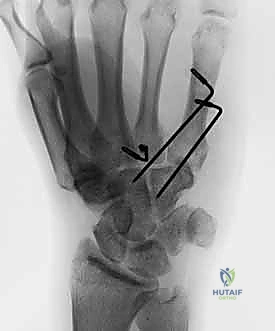

- صور الأشعة السينية المتخصصة (X-Rays): لا يكتفي الدكتور بالصور التقليدية، بل يطلب وضعيات تصوير خاصة (مثل الوضعية المائلة Oblique View بـ 30 درجة) التي تظهر قاعدة المشط بوضوح وتكشف الخلع الخفي.

* الشرائح والمسامير الدقيقة (Mini-Plates & Screws): في حالة الكسور المفتتة جداً، يستخدم الدكتور شرائح من التيتانيوم متناهية الصغر لتثبيت الكسر بشكل دائم وقوي، مما يسمح بحركة مبكرة لليد.